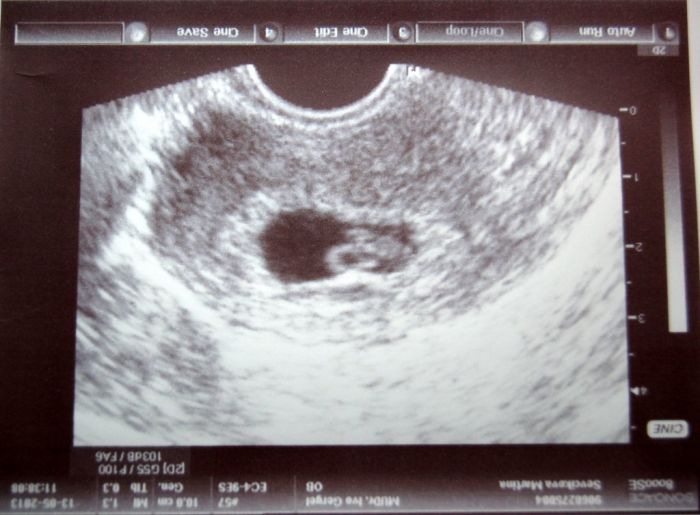

[316312]

Poslední ms byla 19.3. a fotku mimča ze včerejška posílám v příloze :)

[316636] jestli dobře koukám, tak je na tom obrázku míra 16,6, což by mělo být 1,66 cm a to odpovídá tak 8-9 tt, podle kalkulačky tady tito vychází 8+0

[316636] Marti, je úžasná, tvůj Drobek je stejne stary jak Kenatko.:o)))) taky se tesim na fotecku pristi tyden.